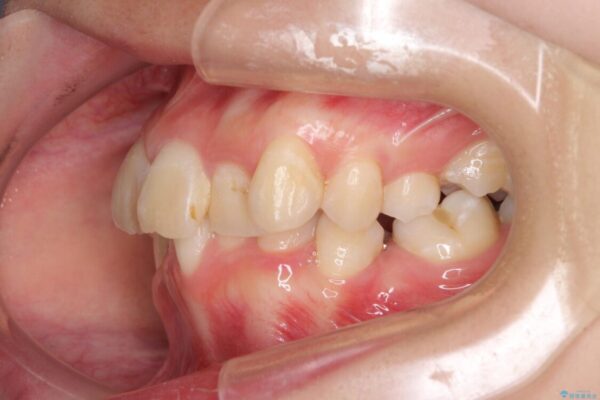

内側に倒れ込んだ歯や下の前歯が隠れてしまうほどの咬み合わせを改善したいとのことで来院された患者様です。

治療前

• デコボコと深い咬み合わせ ワイヤー装置での抜歯矯正 治療前画像